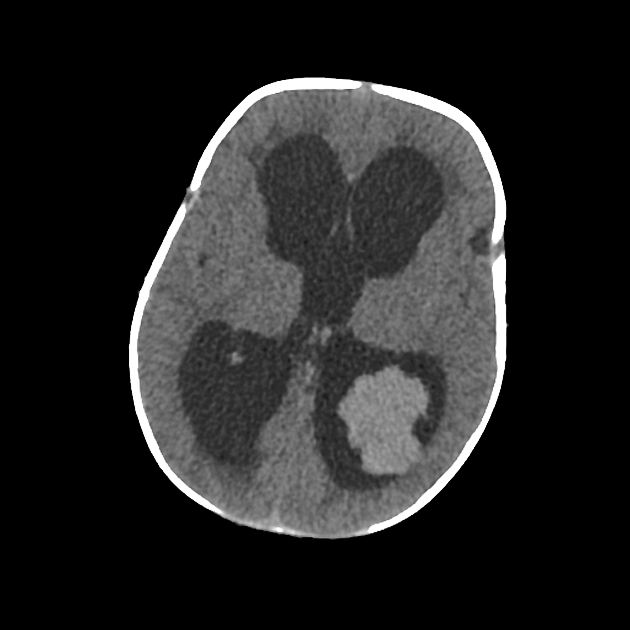

Marked obstructive hydrocephalus due to fourth ventricular outlet obstruction by fine septations

dandy walker malformation

This case illustrates a classic Dandy Walker malformation with associated aqueduct stenosis and obstructive hydrocephalus, a common associated feature

(although not part of the Dandy walker triad: